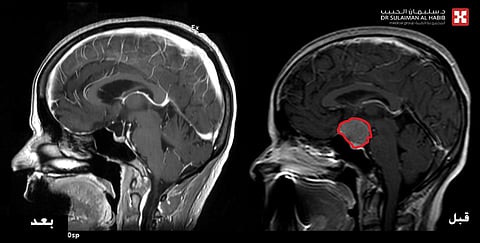

وقال الدكتور ديفيد: إنه تمّ إخضاع المراجعة لفحوصات بالرنين المغناطيسي "M.R.I"، وعدد من التحاليل المخبرية، مشيرًا إلى أنّ نتائج الفحوصات كشفت عن وجود ورم بقطر "3" سم، متمركز في قاع الجمجمة بمنتصف الدماغ، وضاغط بشدة على عصبَي البصر والغدة النخامية المسؤولة عن الهرمونات بالجسم، وعقب مراجعة كافة الفحوصات قرّر الفريقُ الطبي التدخلَ الجراحي العاجل لاستئصال الورم؛ للحيلولة دون إصابة المريضة بمزيد من المضاعفات الخطيرة أبرزها فقدان البصر بشكل كامل، بالإضافة إلى ازدياد حدة الأعراض وحدوث خلل بهرمونات الجسم.

مضيفًا: أنه عقب اتخاذ كافة التدابير اللازمة، تمّ إخضاع المراجعة لعملية دقيقة استغرقت 8 ساعات متواصلة تحت التخدير الكامل، باستخدام الميكروسكوب المتطور "Pentero"؛ إذْ تمّ تحرير الورم بحرص شديد من التصاقاته بالعصب البصري والغدة النخامية واستئصاله بالكامل.